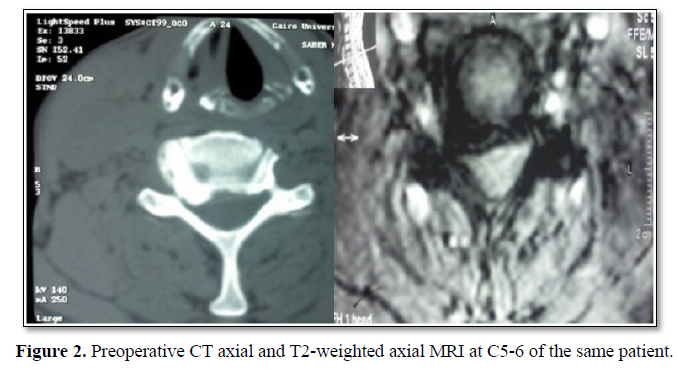

Cervical radiculopathy is a clinical diagnosis defined by the presence of sensory or motor deficits caused by mechanical compression of the corresponding cervical nerve root. Degenerative etiologies include disc herniation, spinal canal stenosis and spondylotic foraminal stenosis [1] (Figure 1). Cervical radiculopathy caused by posterolateral disc herniation can be managed by either an anterior or a posterior approach. The posterior approach was originally reported by Mixter and Barr [2]. The keyhole posterior foraminotomy was described by Spurling and Scoville [3].

The posterior laminoforaminotomy preserves cervical range of motion minimizes adjacent segment disease [4]. The conventional anterior cervical approaches use the surgical plane between medially trachea and laterally great vessels (carotid and jugular vein); and view the spine almost in face. These approaches can be called as anteromedial approach. On the other hand, anterolateral cervical foraminotomy approach retracts the great vessels medially, uses a more lateral angle of view, and views the spine obliquely [2,5-8] (Figures 2 and 3).